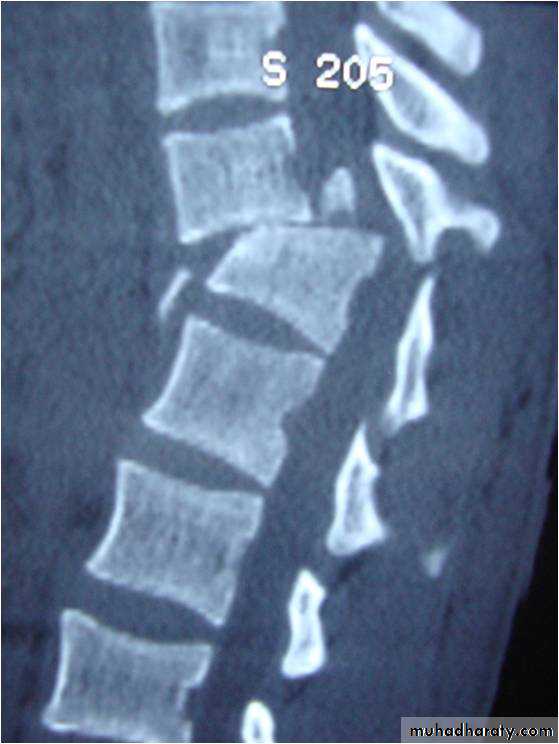

Fracture-Dislocation:

• Failure of all columns (compression, tension,rotation, or shear).• anterior hinge is disrupted.• Dislocation.• the highest incidence of neurological deficit.